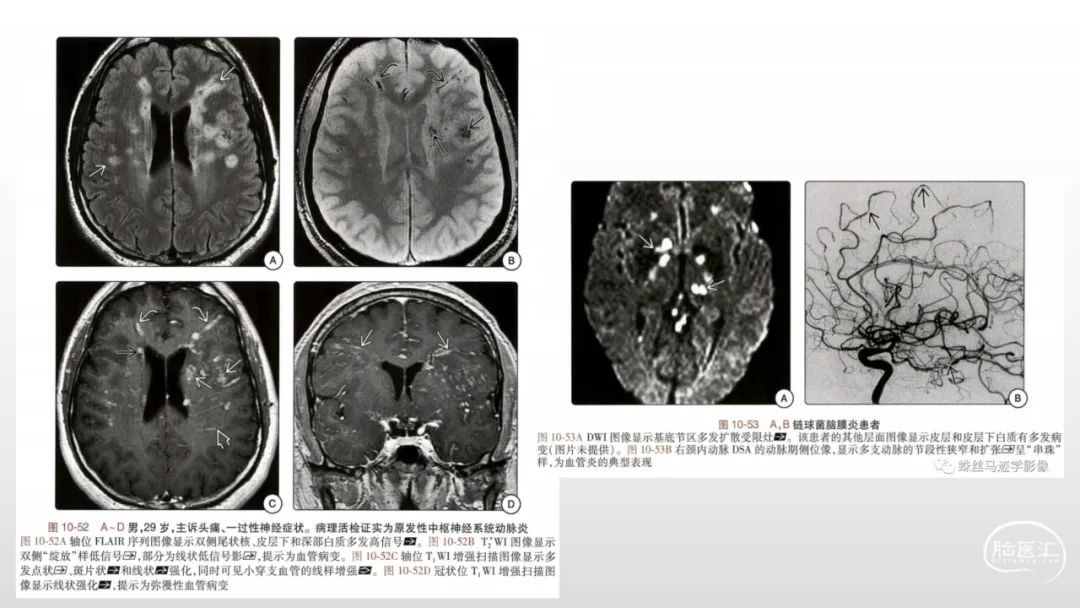

颅脑影像诊断基础知识讲座:《脑血管病》之出血、血管畸形、动脉炎及神经卡压